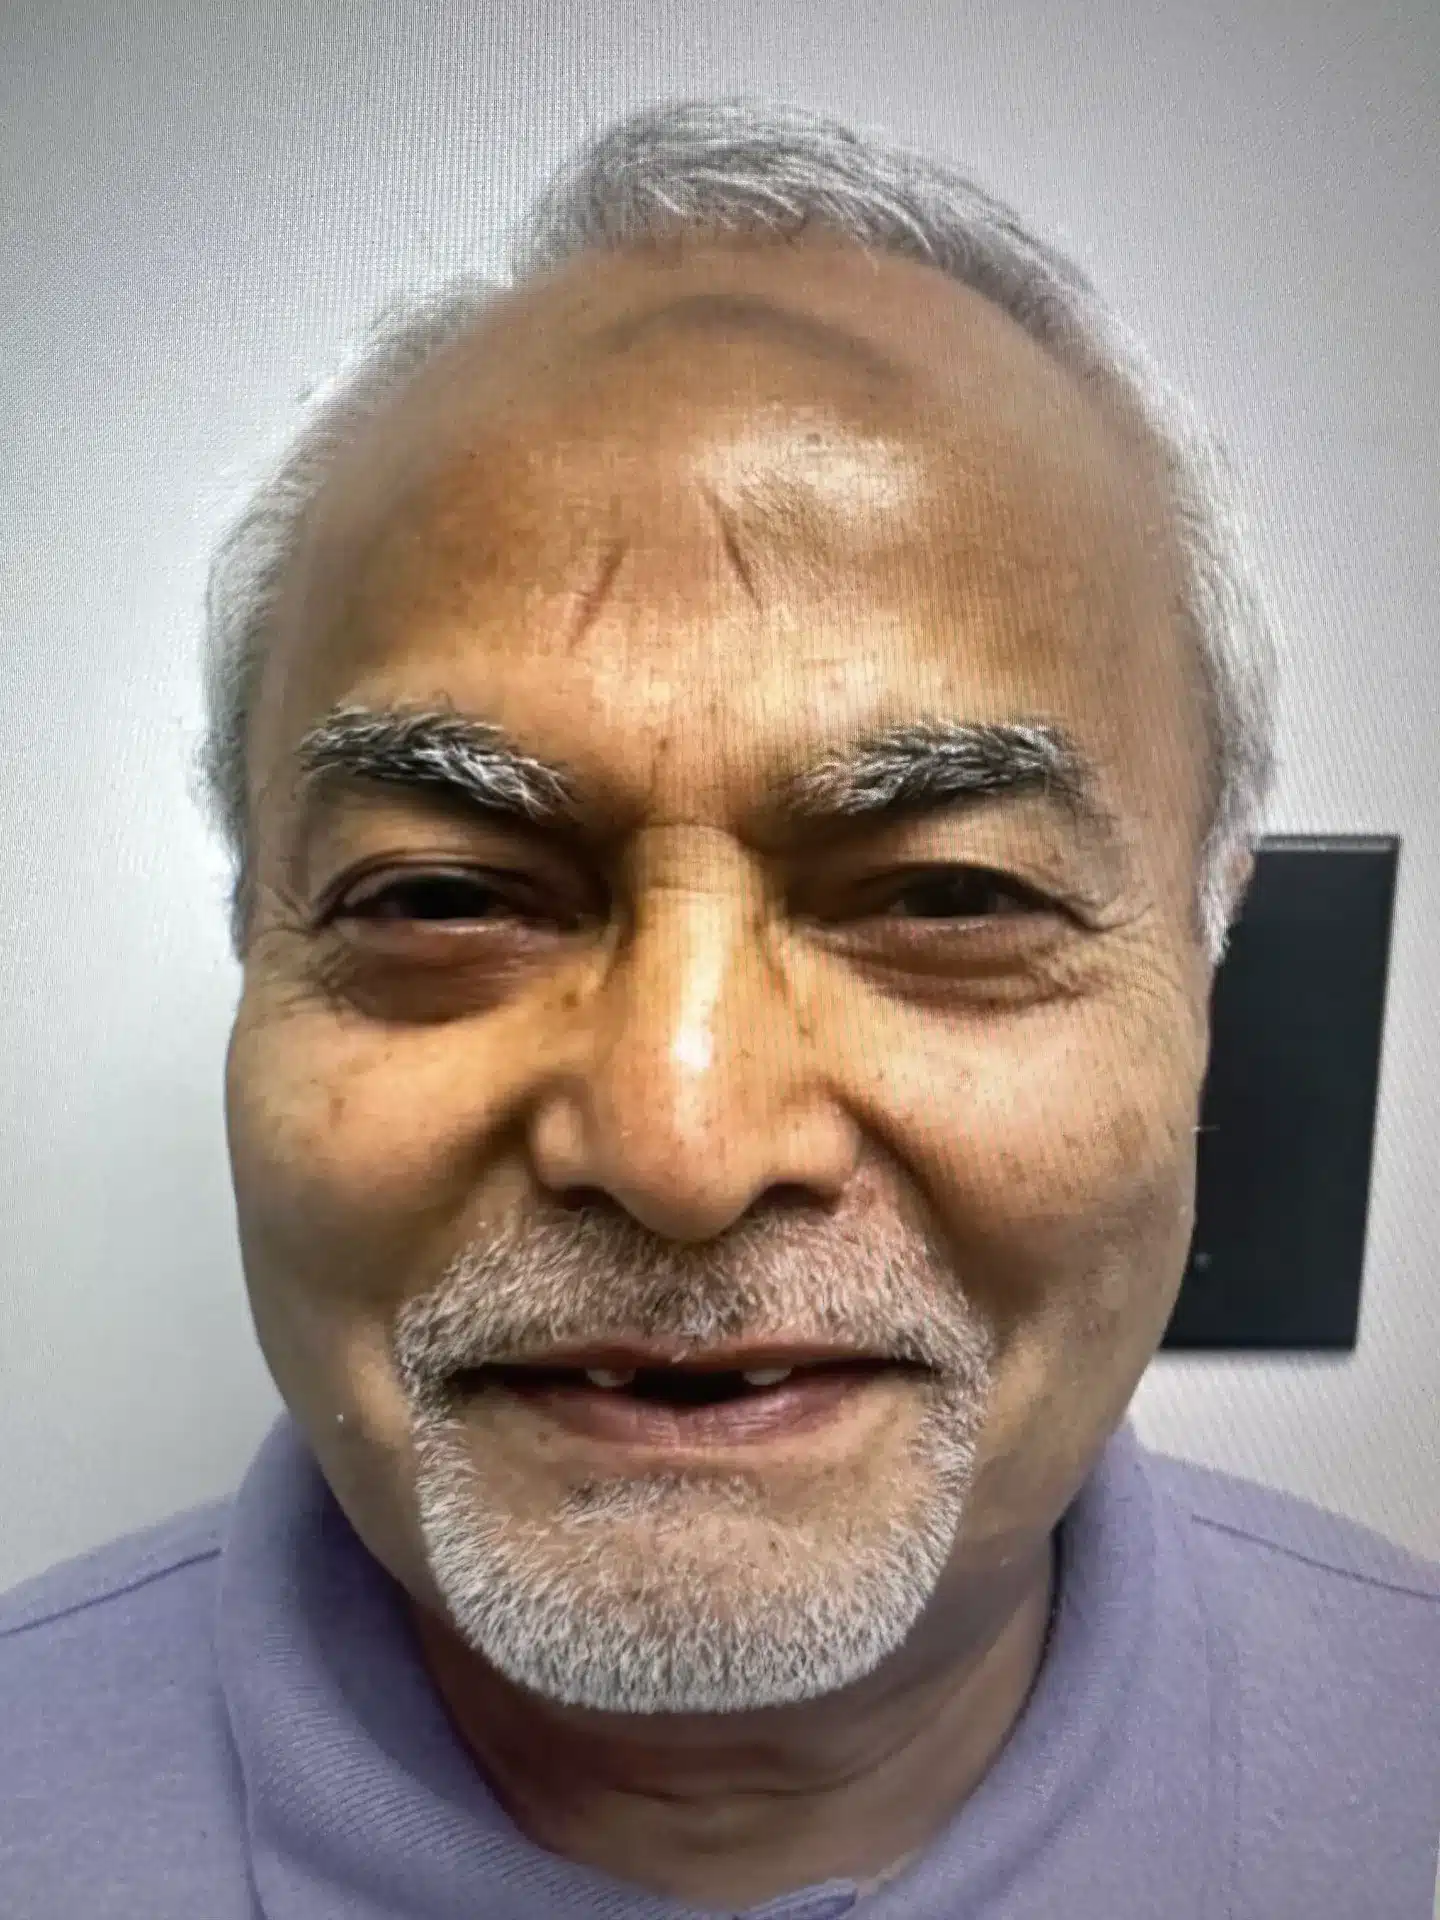

Single Implant Case

Before